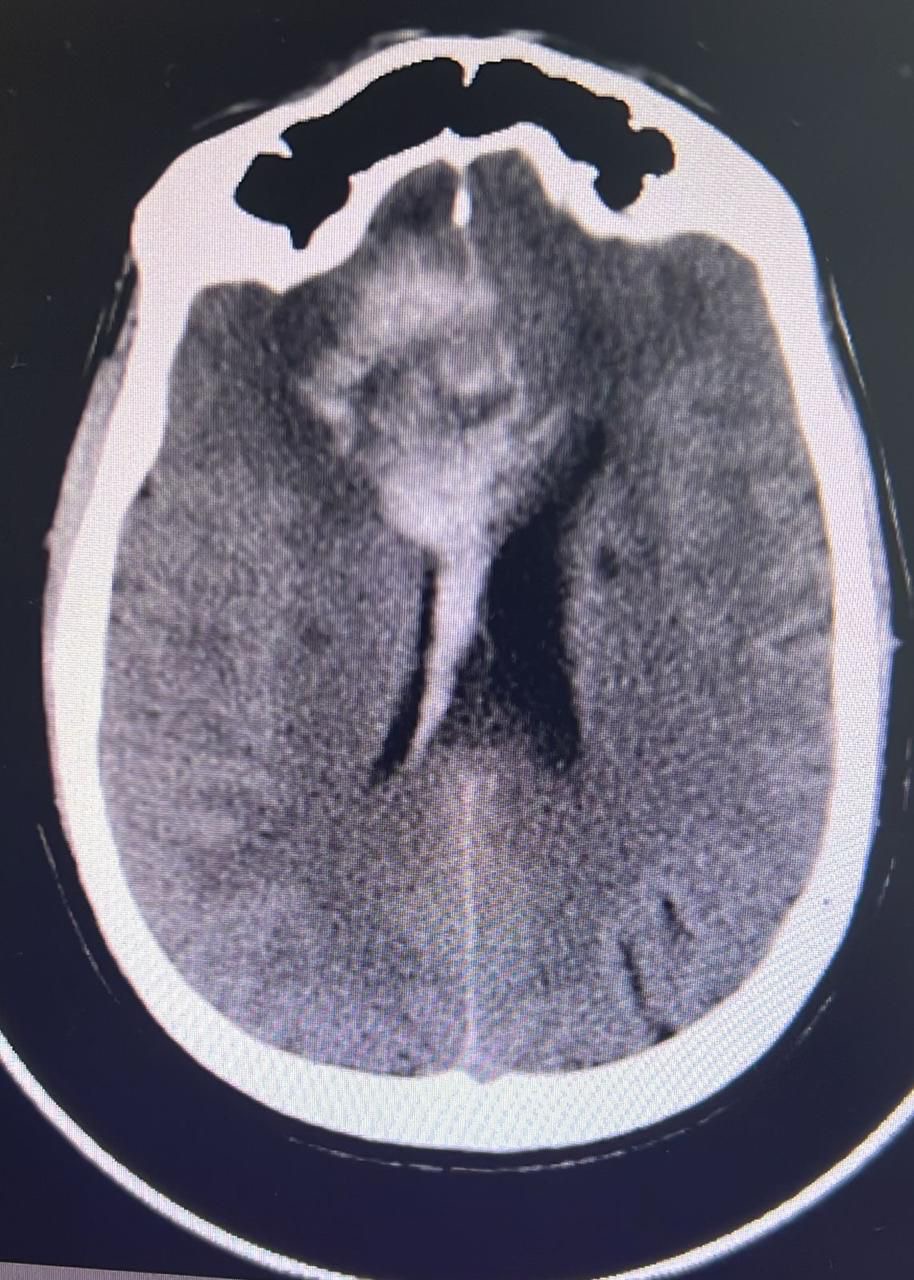

أوضح الدكتور/ أنور الهاشم استشاري و رئيس قسم جراحة المخ والأعصاب والعمود الفقري ، أن المريض استُقبل في طوارئ مجمع الدمام الطبي حيث يشكو من آلام شديدة في الرأس وشلل نصفي وغير قادر على الحركة في الجهة اليمنى وبعد التحاليل والأشعة الدقيقة تبين معاناته من تمدد اوعية دموية في الفص الأيسر من الدماغ وتم التشخيص بأنها السبب في انفجار الشريان الوسطي الدماغي الأيسر. حيث أظهرت الفحوصات الإشعاعية تلفًا في مراكز الحركة في الفص الأيسر ونقصًا في التروية مما يعرض الفص للتلف الشديد وفقدان وظائفه بشكل شبه دائم، وبعد عمل فحص التروية الدماغية تبين بأنه يوجد إمكانية استفادة المريض من إعادة فتح التروية الدموية باستخدام تقنية اغلاق النزيف بالقسطرة، من دون أي مضاعفات.

نجح الفريق الطبي في إجراء عملية القسطرة بواسطة فريق وحدة الأشعة التداخلية بقسم الأشعة بمجمع الدمام الطبي. تم ذلك عبر الدخول بشريان الفخذ بفتحة بسيطة باستخدام الإبرة، وتوجيه القسطرات إلى الأوعية الدموية المصابة واستخدام تقنية مزدوجة لاغلاق النزيف بدعامة معدنية . لم تحدث أي مضاعفات بفضل كفاءة الطاقم الطبي.